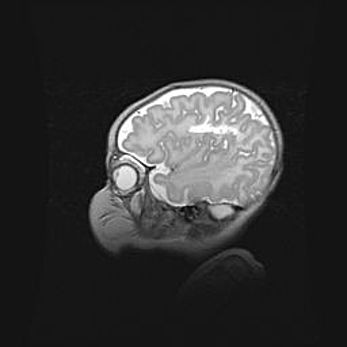

Неполная лизэнцефалия (пахигирия). Открытая гидроцефалия.

Возраст: 17 дней

Вес: 3110 г

Пол: мужской

Окружность головы: 33,5 см

Срок гестации: 35-36 недель

Лизэнцефалия—недоразвитие корковой пластинки и мозговых извилин в результате нарушения миграции нейронов коры. Поверхность мозговых полушарий гладкая. Микроскопически выявляется отсутствие нормальных слоев коры и скопление групп нейронов в подкорковом белом веществе.

Пахигирия—уменьшение числа вторичных извилин. В пораженном полушарии нервные клетки образуют толстый недифференцированный слой с неправильно расположенными нервными волокнами и группами гетеротопных клеток. Нервные клетки незрелые. Белое вещество истончено. При этом нередко аномально развит корково-спинномозговой путь.